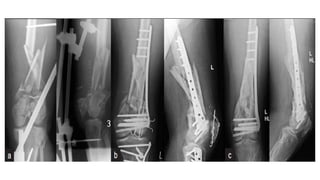

This document discusses femoral fractures, categorized by their location and severity, with classifications such as Garden classification. It outlines the types of fractures, including valgus impacted, non-displaced, partially displaced, and fully displaced, along with their surgical treatment options. Additionally, it briefly describes distal femur fractures, which occur just above the knee joint.